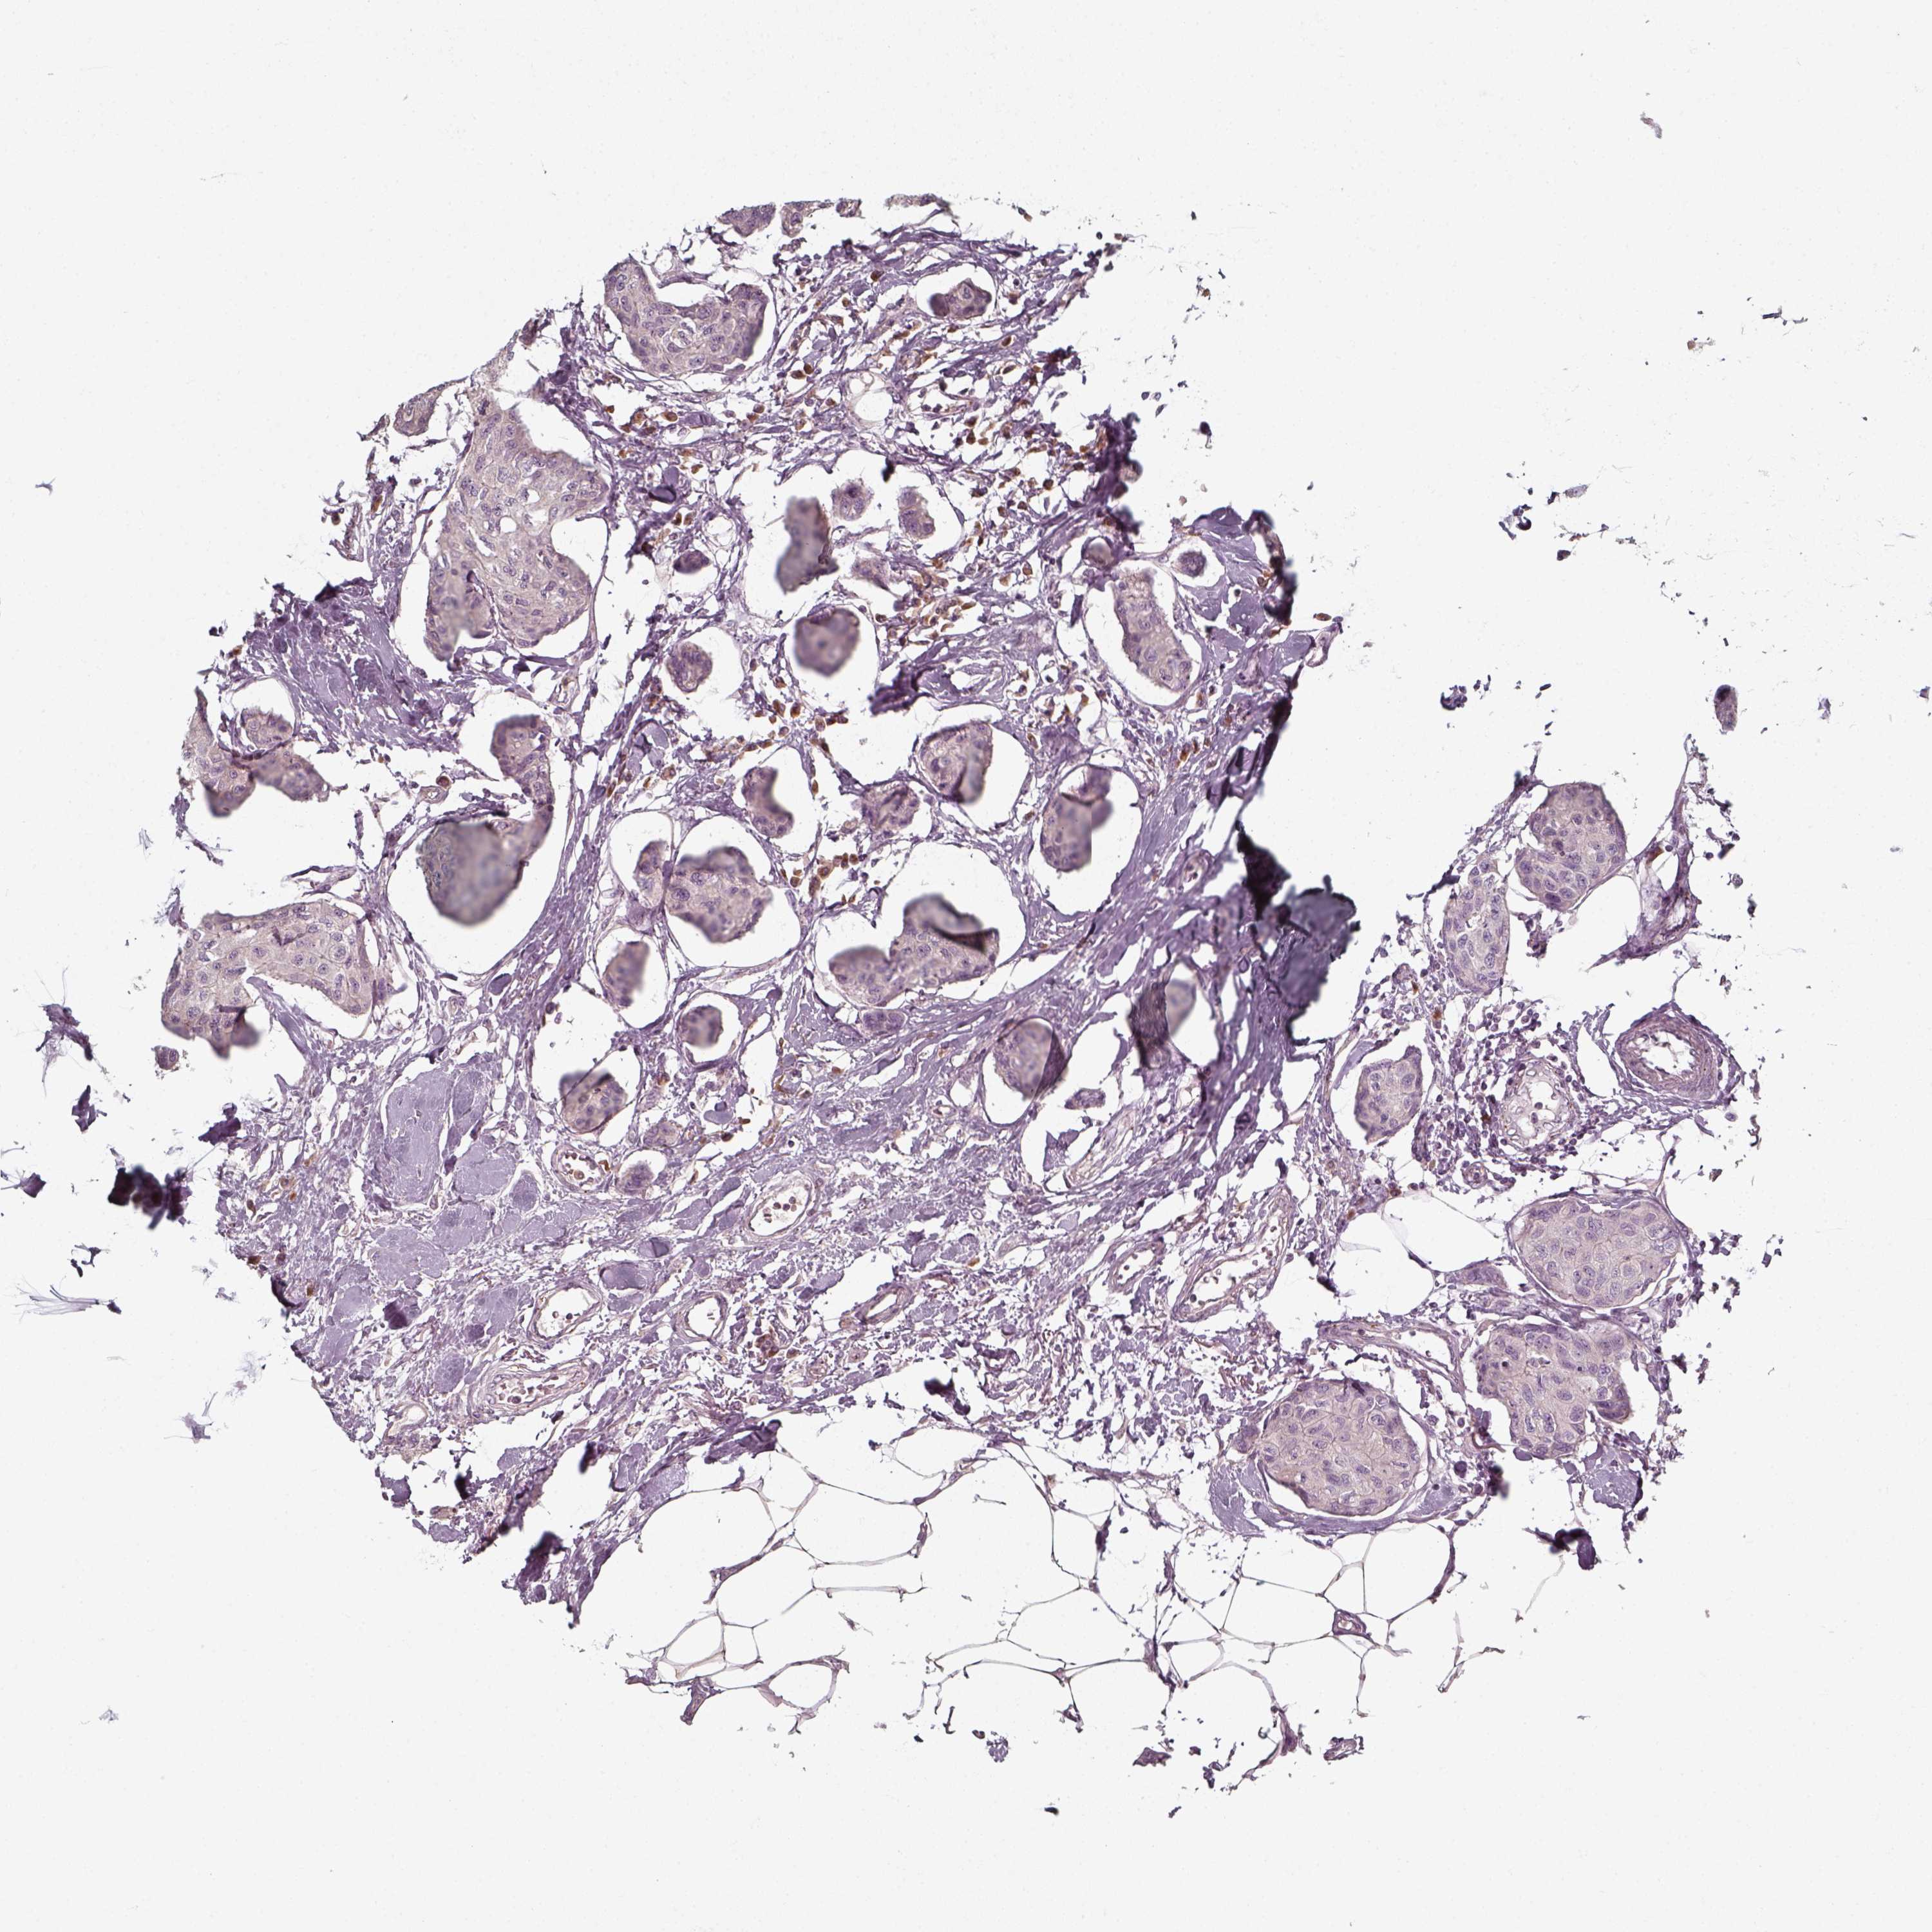

CANCER BREAST CANCER Show tissue menu

BRCA TCGA BRCA VALIDATION PROTEIN EXPRESSION